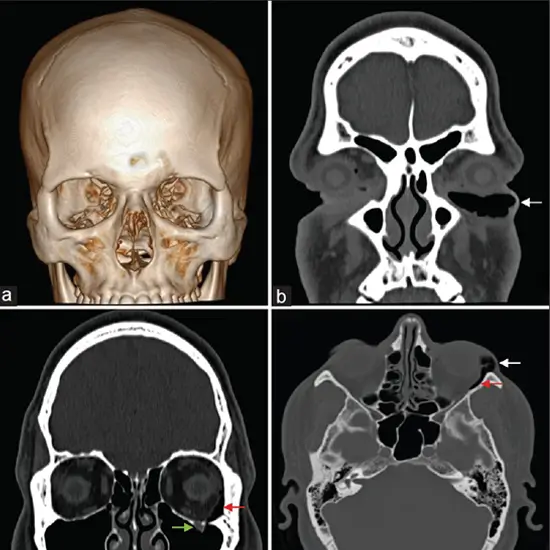

NCCT Orbit Coronal is an imaging scan that is used to diagnose problems in the eye, the sockets, and the surrounding areas. This scan generates extremely thin slice images of the eyes and eye socket. This scan helps the doctor to diagnose injuries, diseases, and congenital defects.

In this scan, the patient will lie straight and still on a movable table. The table will be slid into the machine. Then X-rays from the machine will map the image of the eye, sockets, and the surrounding areas and produce the required image of the orbits of the eyes.